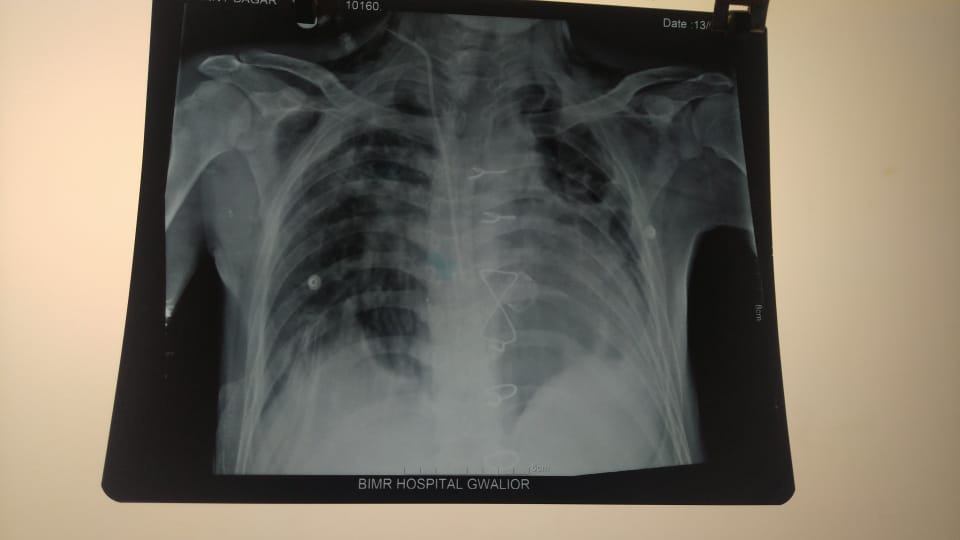

डॉ. शैलेश कुमार यादव, सीनियर कार्डियक सर्जन, बीआईएमआर हॉस्पिटल्स ने एक चुनौतीपूर्ण और जटिल ऑपरेशन किया, 23 वर्षीय पुरुष रोगी का एओर्टिक वाल्व रिप्लेसमेंट किया (EF= 45%, Aortic वाल्व में सीवियर लीकेज था) जिसमें दोनों लंग्स के मल्टीड्रग रेजिस्टेंस टीबी (एमडीआर-टीबी) थे। बायीं तरफ का फेफड़ा पूरी तरह से नष्ट हो गया है और केवल दांयी तरफ का फेफड़ा केवल 30% काम कर रहा था। ऐसी स्थिति में मरीज को ऑपरेशन के बाद वेंटीलेटर सपोर्ट से बहार निकालना काफी मुश्किल था । इस वजह से मरीज को दिल्ली एवं चंडीगढ़ के डॉक्टर ने सर्जरी करने से मना कर दिया था ।